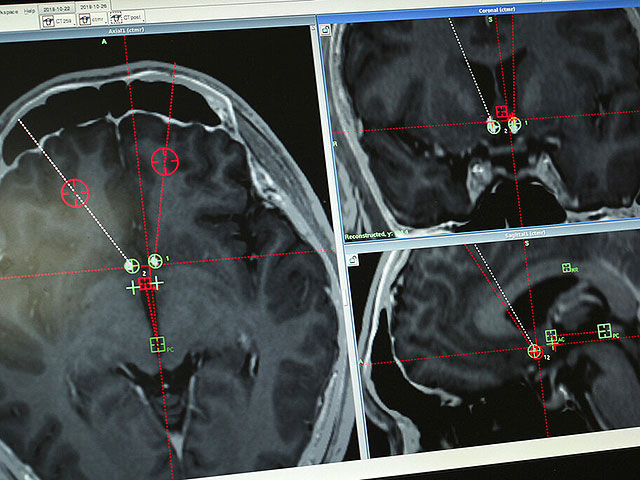

AP Photo/Erika Kinetz